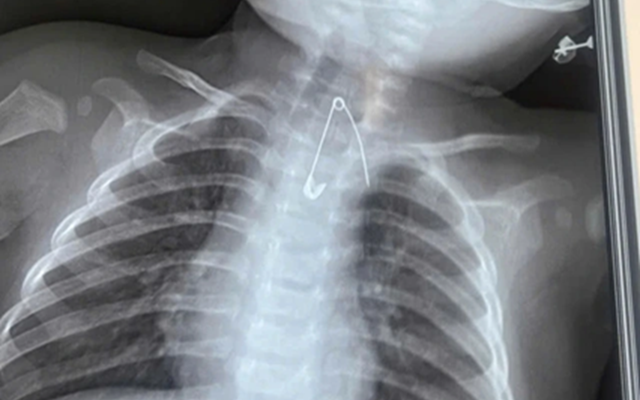

Kim băng nằm sát động mạch chủ bé Đ.

Người nhà cho biết, gia đình có thói quen dùng kim tây (kim băng) ghim bùa bình an vào áo của bé. Qua thăm khám lâm sàng và thực hiện các xét nghiệm cận lâm sàng, các bác sĩ phát hiện một dị vật là kim tây nằm trong mô mềm, ở vị trí sát động mạch chủ, rất nguy hiểm.

Bệnh nhi sau đó được ê-kíp phẫu thuật lấy thành công kim băng, ngăn ngừa các biến chứng nghiêm trọng có thể xảy ra.